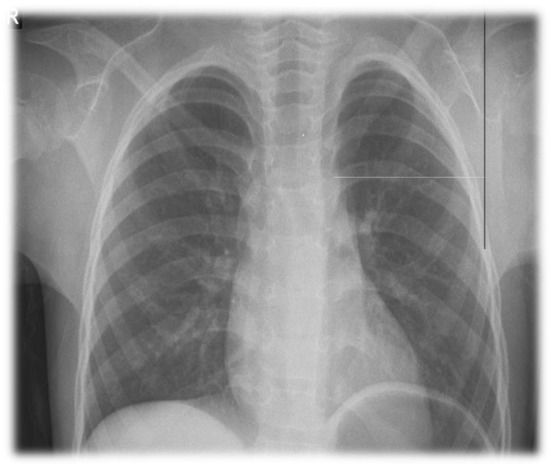

2. Clinical Report

2.1. A General Description of the Patients

2.5. Screening for Comorbidities